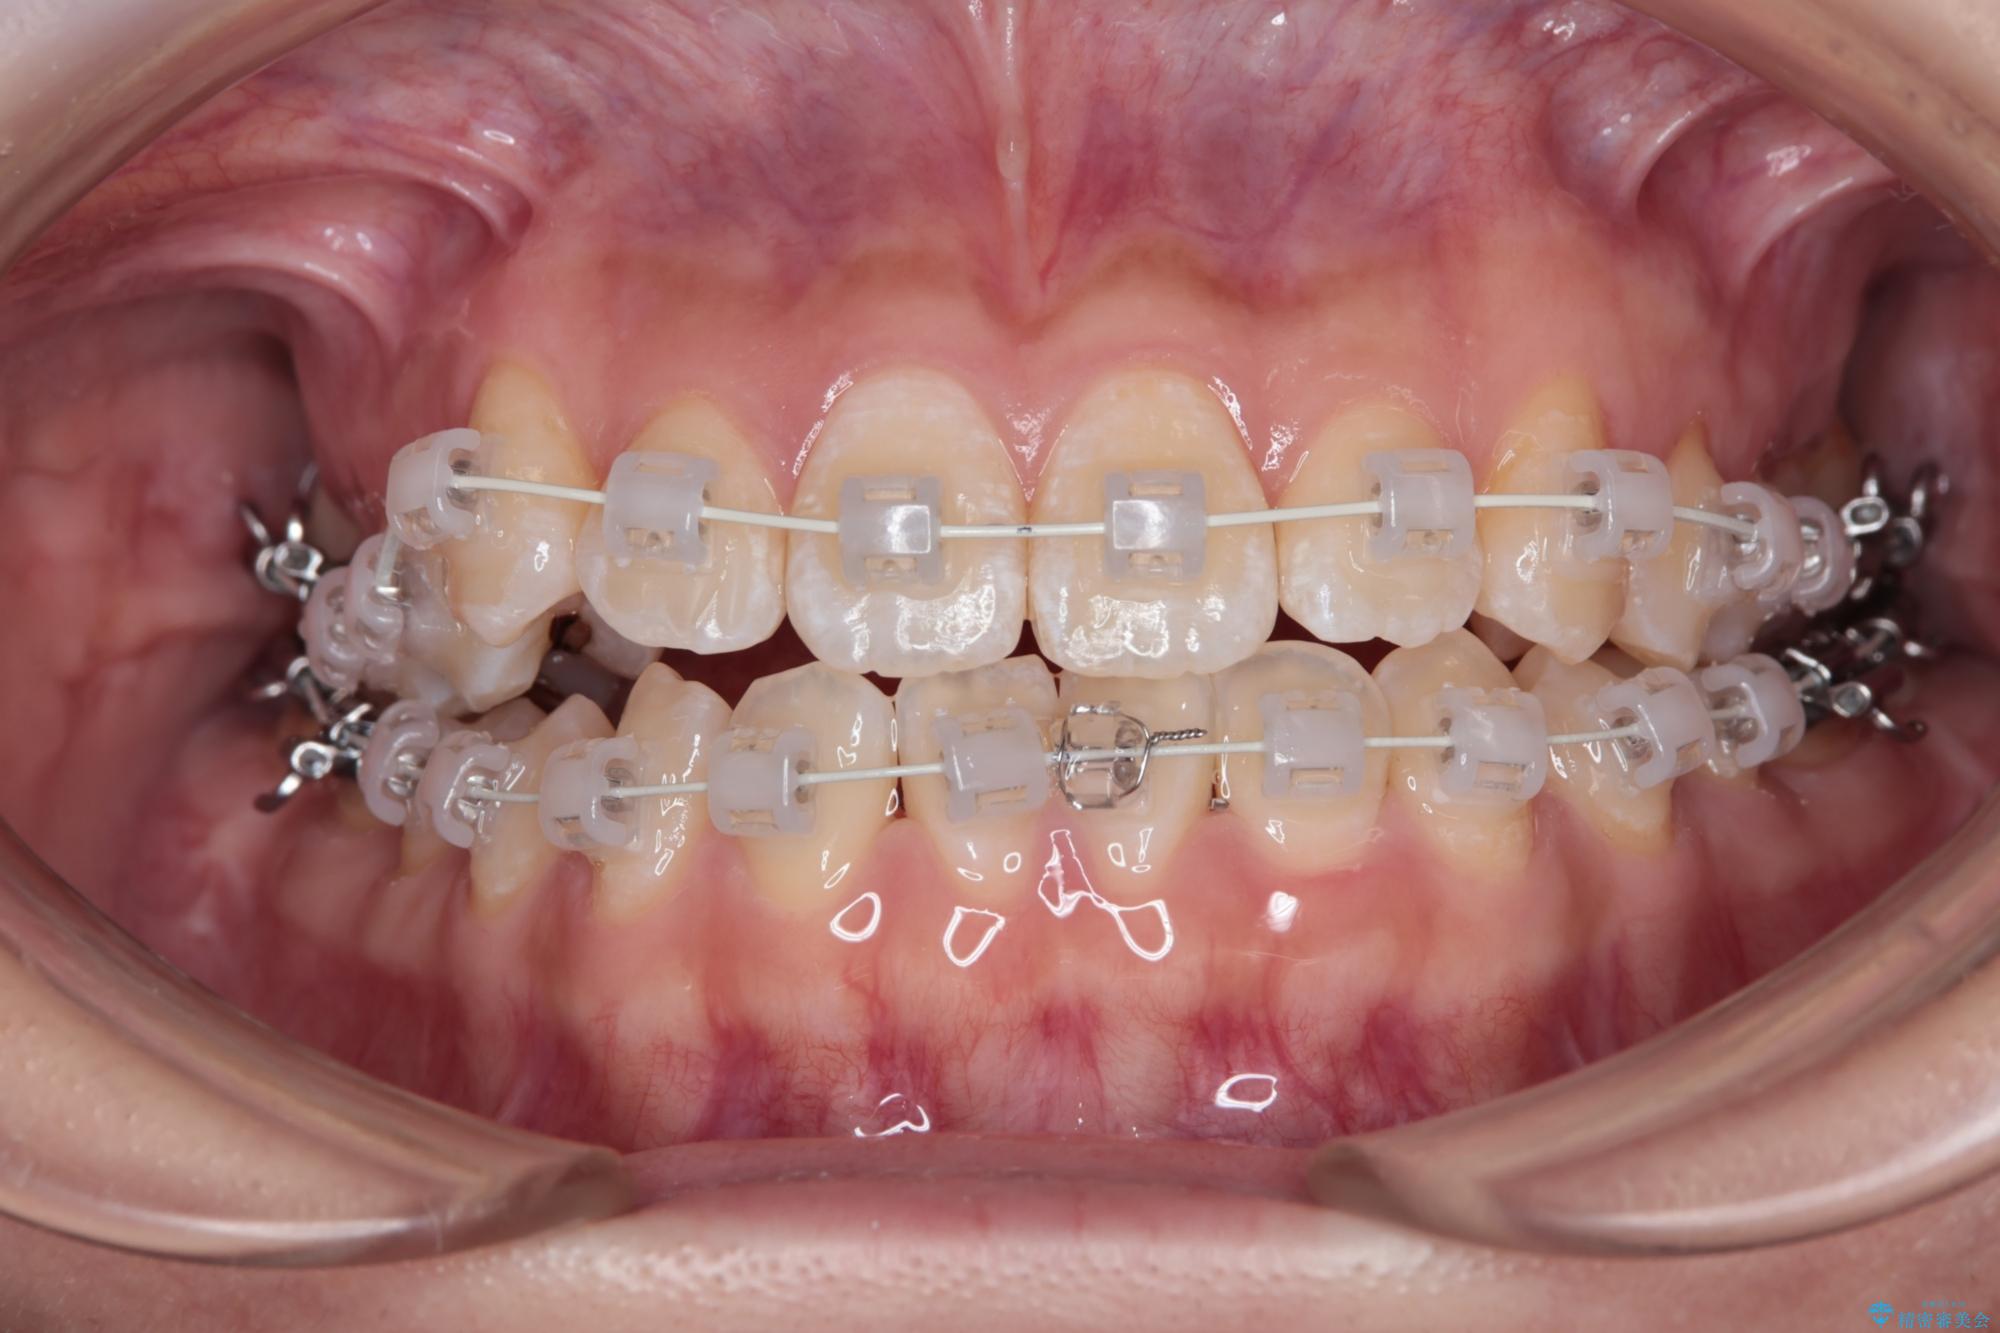

右側の八重歯の部分は噛み合わせをよくするためにゴム掛けを行いました。

また、セラミックと銀歯の部分は装置が脱離してしまうので、矯正用の仮歯に変えて治療を行いました。

予定通り1年で気になっていた八重歯とガタつきが改善され、大変喜んでいただけました。